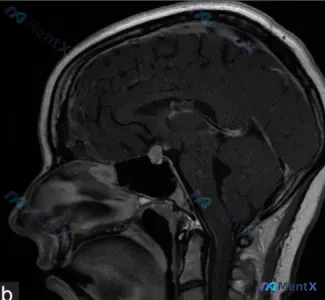

这张鞍区MRI的结节你会怎么考虑?别只盯着肿瘤/感染,这个良性病概率最高

看到一张脑部MRI的图像,整理一下读片和分析思路,和大家讨论。 影像基本信息 - 序列:钆增强T1加权像矢状位(正中矢状位) - 主要观察区域:鞍区及鞍上池 关键影像表现 正常结构 - 中线结构居中,胼胝体、脑干、第四脑室形态正常 - 垂体窝内垂体后叶可见正常T1高信号“亮斑”,垂体柄可见 - 脑室...